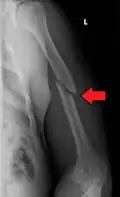

A transverse fracture of the humerus shaft

A spiral fracture of the distal one-third of the humerus shaft